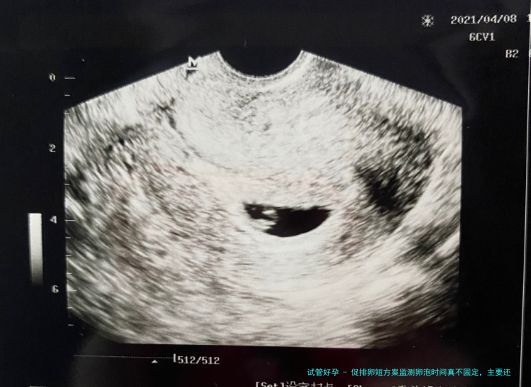

| 卵泡监测 | 月经第10天 |